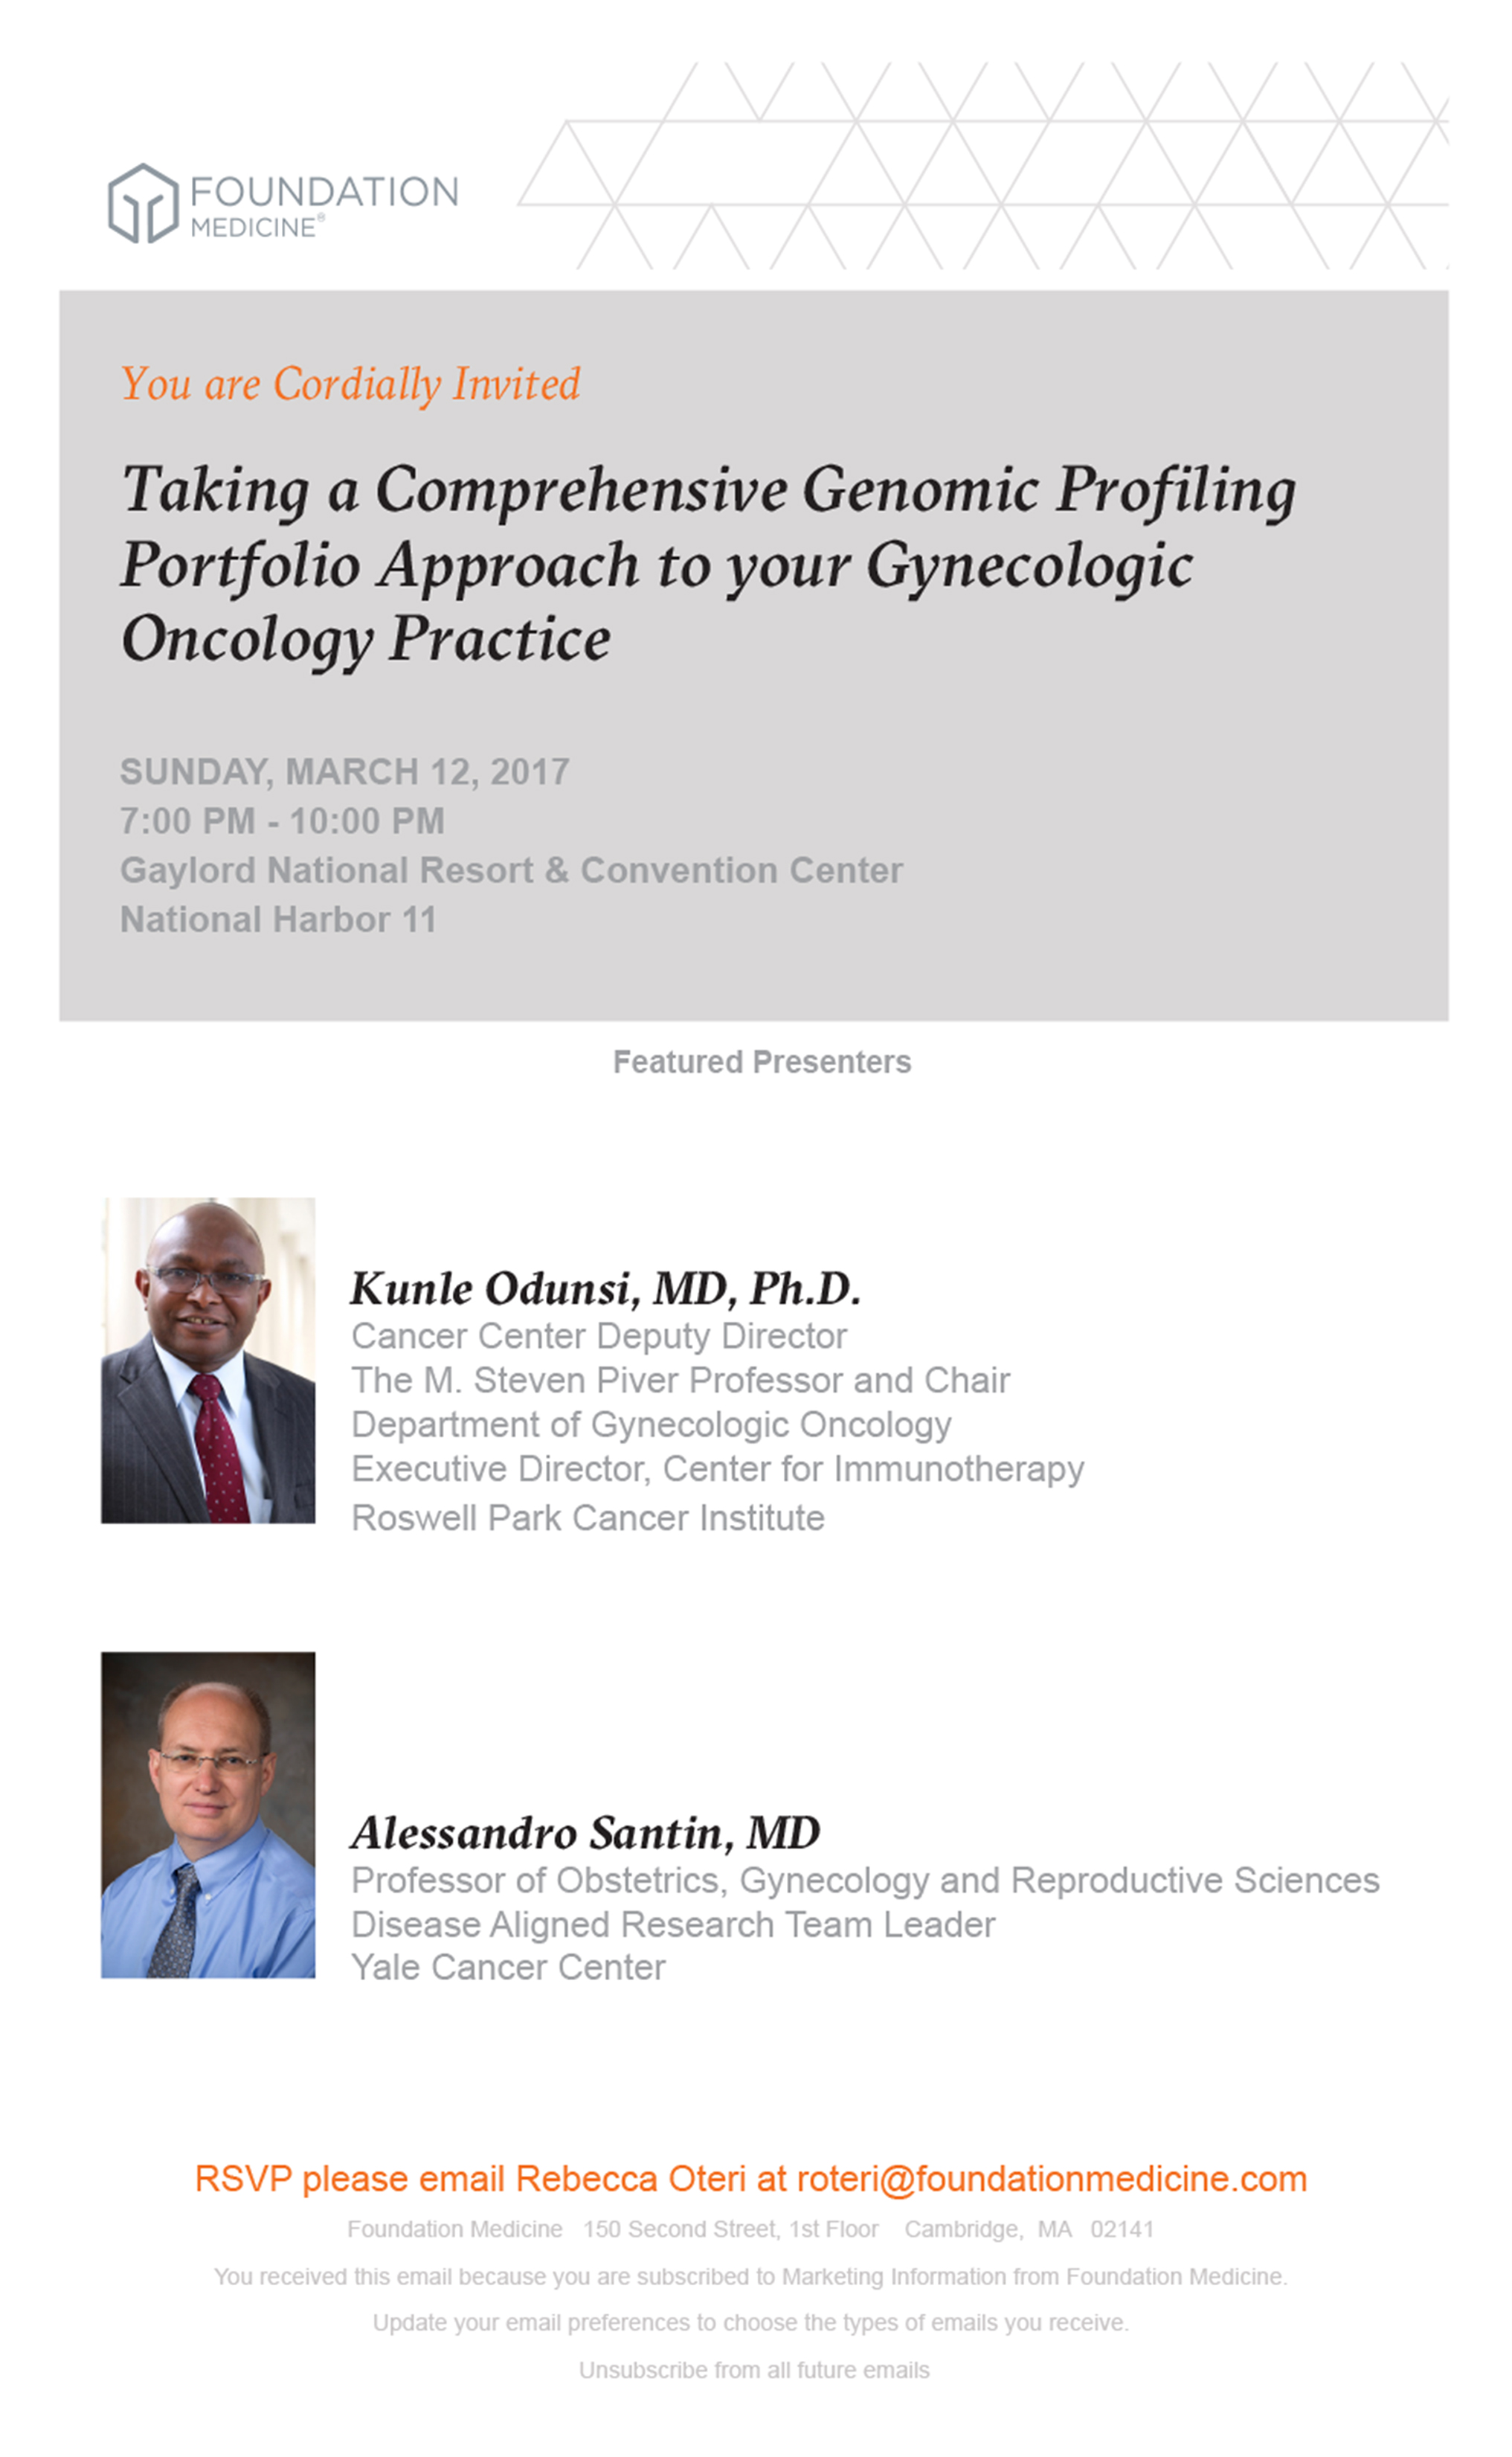

FOUNDATION MEDICINE